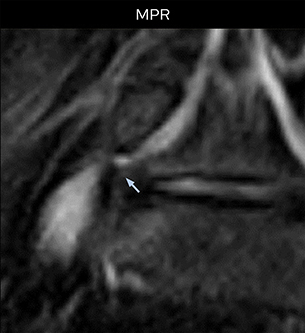

“Although symptoms of typical disc herniation and atypical hernia are very similar, the actual site of herniation is different. It is therefore important to characterize the nerve’s condition both inside and outside of the intervertebral foramina. “Conversely, if we see no abnormality in NerveVIEW, we can assume at least that there is no severe condition that requires surgery. Like this, it can help us avoid unnecessary surgery. NerveVIEW can have a tremendous impact in this way.”

“NerveVIEW is really useful for those cases where a nerve disorder is strongly suspected based on the clinical examination but our regular MRI images do not show any findings. These atypical herniations and spinal canal stenosis, occurring in 5% to 15% of the total lumbar herniation/stenosis cases are our main target when using NerveVIEW,” says Dr. Yabuki.

“The intra-luminal signal of veins, especially around the intervertebral space, can be suppressed well with NerveVIEW. As a result, we can easily observe the detailed nerve structure around the posterior ganglion,” he says. “This is why we use 3D NerveVIEW for intraforaminal stenosis and extraforaminal stenosis/herniation (lateral disc herniation). On the other hand, if herniation is suspected to exist inside the dorsal root ganglion (DRG), balanced TFE or ProSet-FFE is applied. NerveVIEW is not suitable for evaluating the median type of herniation.” The SE-EPI DWI-based method for MR neurography works well for large FOV exams like whole-body MRI, but focal examination of nerves is often limited by the attainable spatial resolution (both inplane and slice direction) and geometric distortion. “3D NerveVIEW achieves higher in-plane resolution – close to our other routine spine sequences – and the source images can be used instead of adding a fat-suppressed T2-weighted sequence,” Tanji says.